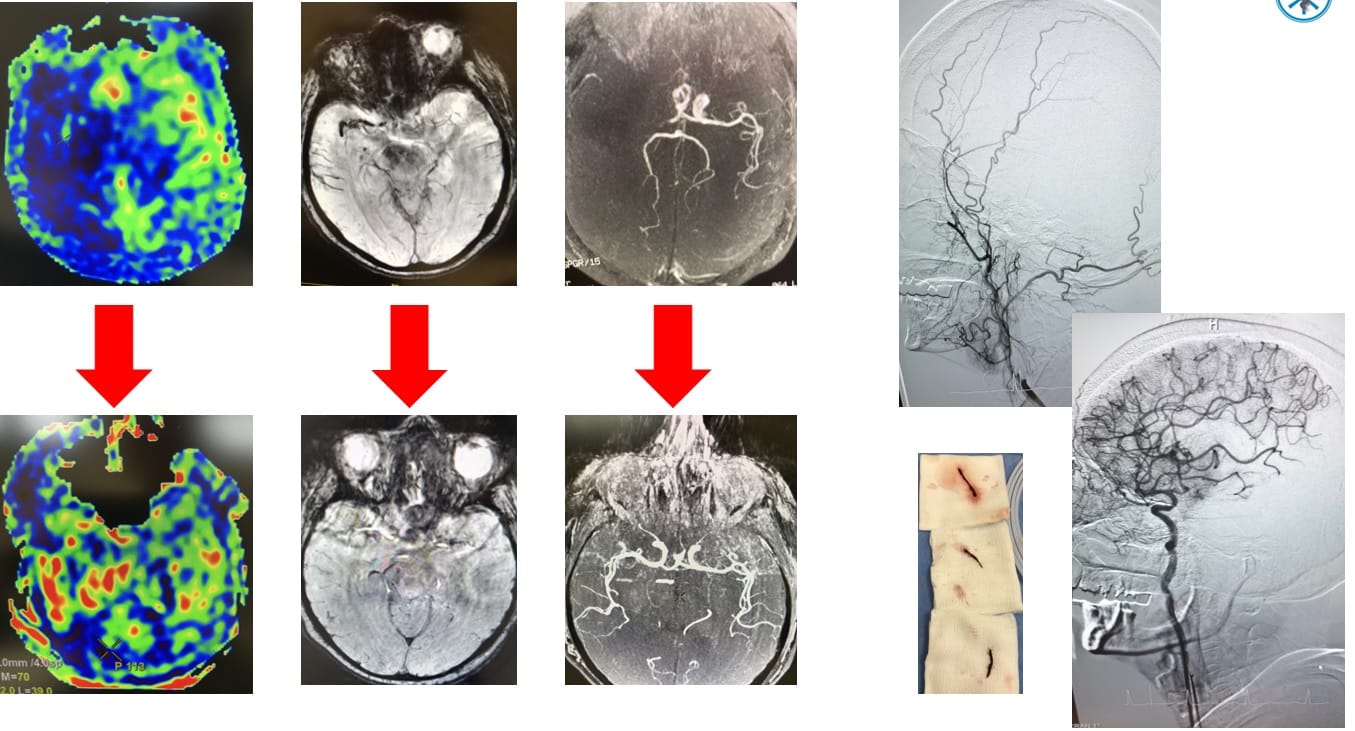

Nakon što je magnetnom rezonancom utvrđeno da pacijentkinja doživljava moždani udar, tim neurologa i radiologa niškog Kliničkog centra prošle nedelje je uspešno po prvi put u ovoj ustanovi kombinovao dve procedure – direktno “usisavanje” tromba vakuumom i ugradnju karotidnog stenta.

Niški lekari prvo su 65-godišnjoj pacijentkinji spasili moždano tkivo koje izumire zbog ugrušaka u krvnim sudovima, i to sistemom “Penumbru” koji se na Klinici za neurologiju uspešno primenjuju poslednje četiri godine.

Raniji stavovi ukazivali su da je za uspeh terapije ključno vreme, odnosno da se povoljan terapijski ishod može očekivati uglavnom kod bolesnika koji su tretirani unutar 6 sati od početka simptoma, međutim sada smo pokazali da i u vremenskom okviru od 12 sati možemo spasiti moždano tkivo. Osim što je to bila osma „Penumbra“ naših neurologa, ona je uspešno kombinovana sa stentiranjem moždanog krvnog suda, istakla je prof. dr Miroslava Živković, direktorka Klinike za neurologiju.

Kako su pojasnili neurolozi, ovo je jednostavna i brza tehnika vakuum aspiracije tromba kod zapušenja velikih krvnih sudova u mozgu. Zatim je pacijentkinji ugrađen stent na delu karotidne moždane arterije.